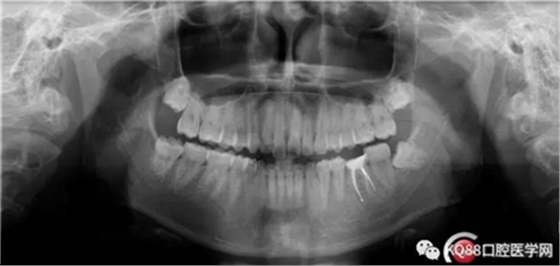

充填完成,暫時觀察一周。下一步做牙冠延長,近遠中打纖維樁,全冠或嵌體修復(fù)。

一周后復(fù)診,無明顯不適。擬樁,全冠修復(fù)。

首先預(yù)備樁道,樁道預(yù)備完成,用樹脂封閉根管口。嵌入兩根纖維樁。樁核粘結(jié)劑做基。